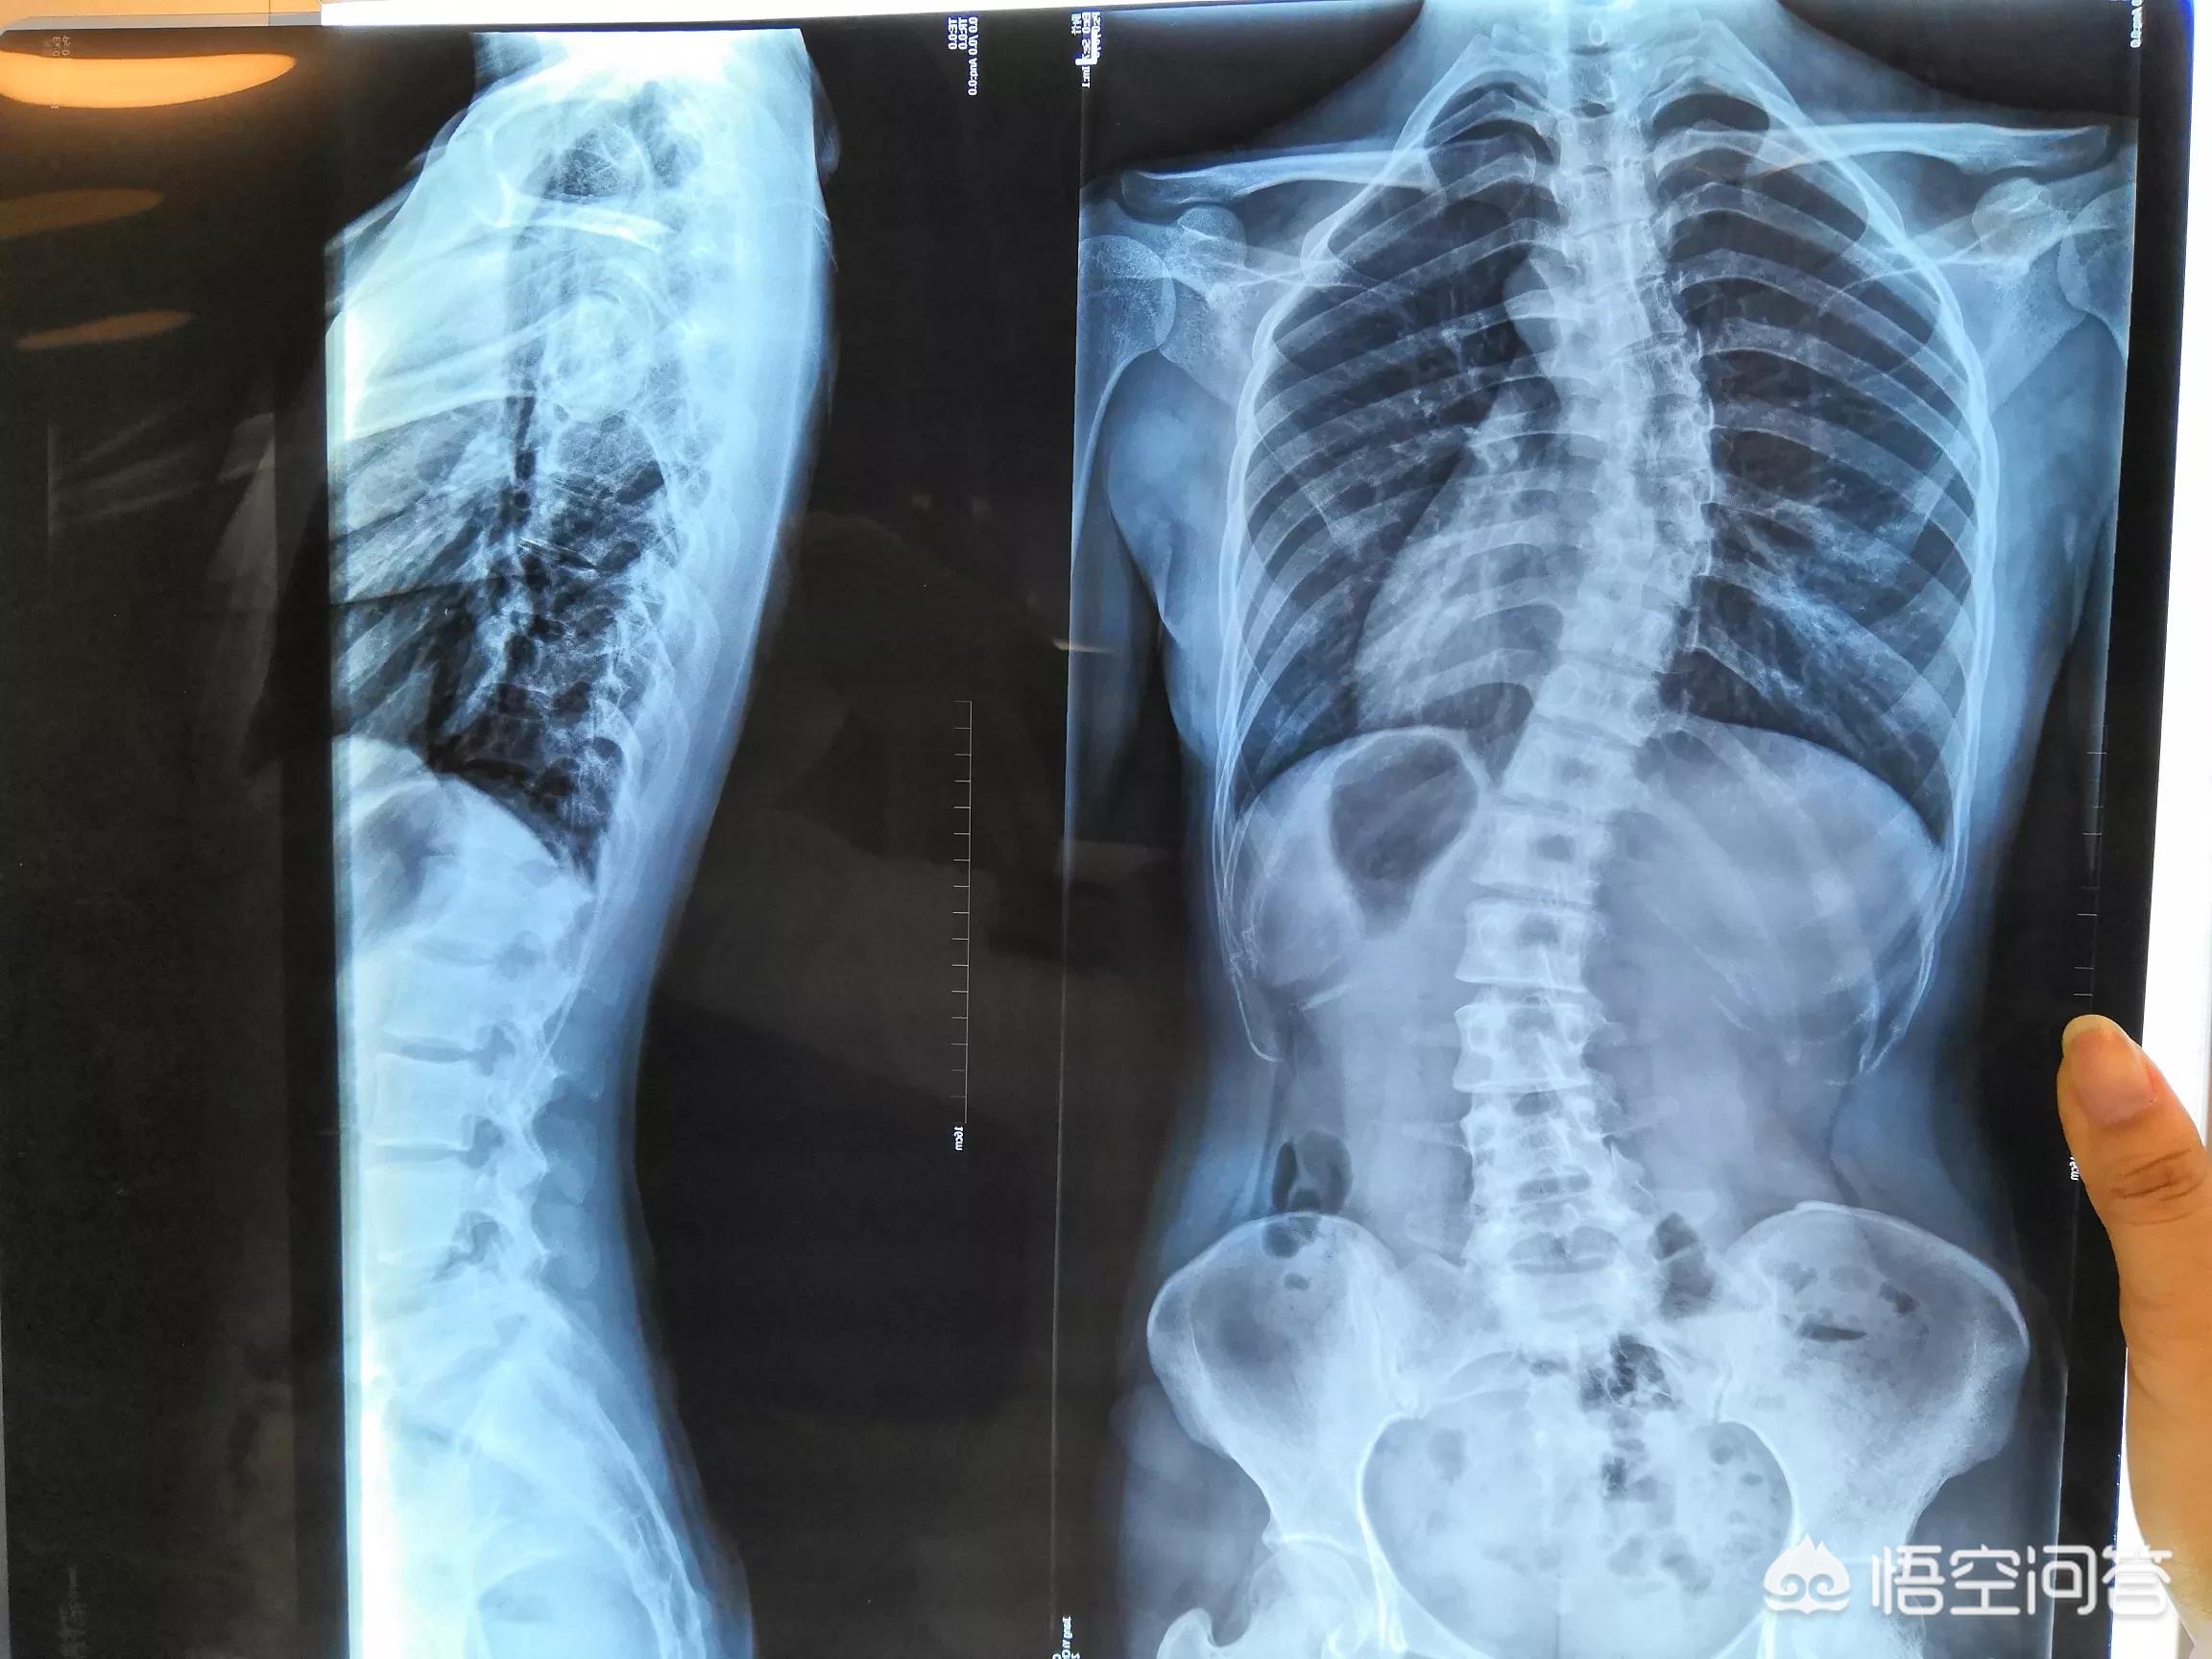

从专业上讲叫脊柱侧凸,是指脊柱在冠状位、矢状位出现失衡引起的一个畸形,脊柱侧弯往往是在通过X线表现冠状位超过10度,就被诊断为脊柱侧弯,轻度的脊柱侧弯小于10度以上的,或者20度以上的脊柱侧弯,会带来外观上的一些改变,如果是大于40度以上的脊柱侧弯,往往会带来明显的一个外观改变,严重的会影响到脊柱内的脊髓、神经功能,进而引起临床症状,因此轻度的脊柱侧弯可以选择观察,严重的脊柱侧弯往往是选择需要手术治疗。

1,结构性脊柱侧弯,就是先天性发育缺陷,出现椎体结构问题,严重的从婴儿时就会出现,随身体生长越来越严,角度有可能在100度以上,身体明显变形扭曲,需要手术结合长期的康复训练调整,减少其它后遗症的发生。

这是比较严重的结构性脊柱侧弯,达到了133度,内脏位置和功能都受到影响。

2,代偿性脊柱侧弯,就是指没有先天性椎体发育缺陷,但在后天生长中,太多的不良习惯,而出现脊柱侧弯,通常角度不大,但患者有明显的疼痛不适,80%的患者多发于快速生长的青春期。

第二、根据严重程度来分类。分为轻度、中度、重度以及极重度。Cobb角在40度到80度之间为中度的脊柱侧弯,Cobb角大于80度的往往是重度脊柱侧弯。小于40度的轻度脊柱侧弯可以通过保守治疗,例如支具、体育运动锻炼等等。40度到80度之间的中度脊柱侧弯,通过支具是没有太大的效果,有可能会影响到患者的心肺功能,需要考虑手术治疗。